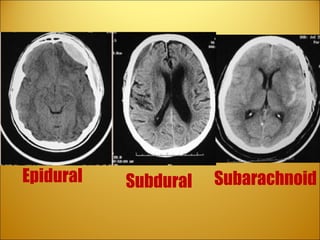

Epidural hematoma .  Usually s/p  head trauma . Brief  +LOC, followed by lucid period.  Then drowsy/coma/death . A well-defined  biconvex  collection of blood (arrows) compresses the left cerebral hemisphere. There is inward displacement of the grey-white junction (arrowheads) and slight rightward displacement of the left lateral ventricle.

Subdural hematoma :   a  concave  collection of  venous blood between the dura and the arachnoid   (resulting from tears of the bridging veins that extend from the subarachnoid space to the dural venous sinuses.) Patients with cortical atrophy, such as alcoholics and the elderly, are more susceptible to subdural hematoma formation when undergoing acceleration-deceleration forces during  head trauma .  After 2 weeks, patients are defined as having a chronic subdural hematoma, which appear hypodense on a CT scan.

Subarachnoid hemorrhage :   results from the disruption of subarachnoid vessels presents with  blood in the cerebrospinal fluid .  Not a space occupying lesion, “pero” can lead to increased ICP and acute hydrocephalus Patients may complain of  headache, photophobia, and have mild meningeal signs . Noncontrast CT is diagnostic in most cases (95%) If CT is neg, but clinical suspicion is strong do LP “ Worst HA of my life” “ Thunder-clap HA”  Sudden Onset

Review Subarachnoid ? Subdural ?   Epidural ?

Review Subdural   Epidural  Subarachnoid